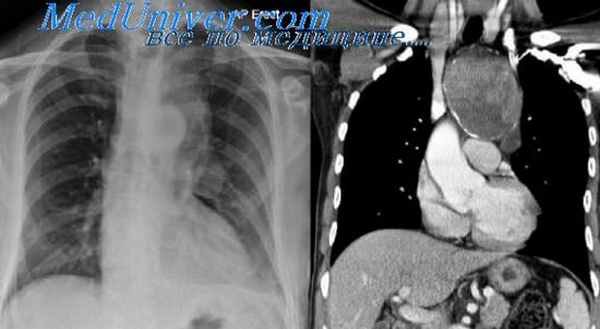

В тех случаях, когда эти опухоли (что, к счастью, бывает редко) озлокачествляются и приобретают крупные размеры, тогда судить о природе, источнике чрезвычайно сложно. Это злокачественная нейрогенная опухоль, которая привела к оттеснению средостения в противоположную сторону – в сторону правого легкого с накоплением жидкости в правой половине плевральной полости.

Огромных размеров патологическое образование, оттесняющее аорту впереди в сторону сердца, занимающее практически всю левую половину грудной полости, оттесняющее селезенку, почку и диафрагму вниз. Это злокачественная нейрогенная опухоль. Но сказать о том, что эта опухоль исходит из нервных образований, при томографическом исследовании очень сложно и не всегда возможно.